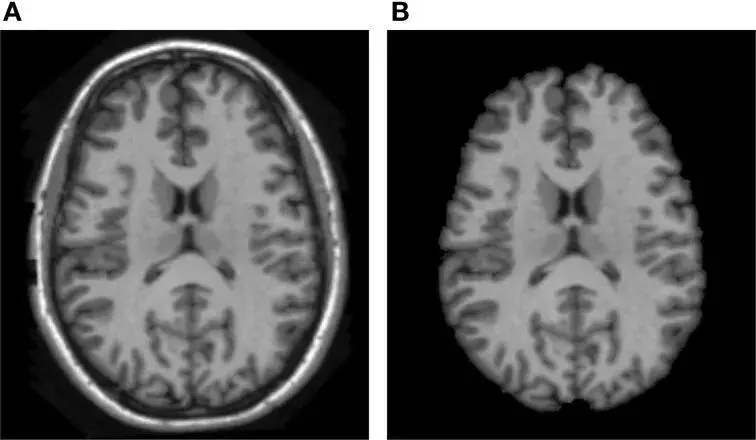

如前文所述,当亮度值受到诸如噪声、PVE、偏压场效应等MRI误差的影响时,基于亮度的图像分割算法非常容易出错。因此,引入并利用待分割图像的空间信息就非常重要。此时,提取的结果可以用一个 mask 来表述,也可以生成一张如下图B所示的只有脑部组织的新图片,再送入分割算法。

脑部组织提取示意图。A. 原始MRI图像;B. 脑组织提取结果